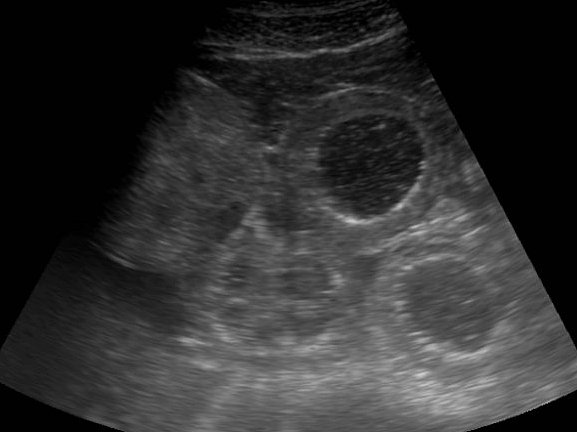

Ultraschall

Die ultrasonographische Untersuchung findet in der Pferdemedizin ein vielfältiges Einsatzgebiet, da sie für die Darstellung von Weichteilstrukturen wie z.B. Sehnen, Bändern, Darm und Organen wie Herz und Nieren besonders geeignet ist. Die Klinik für Pferde verfügt über mehrere hochmoderne Ultraschallgeräte, die für spezielle Fragestellungen (z.B. Herzultraschall oder Sehnenerkrankung) zur Verfügung stehen.

Deshalb wird die Ultraschalluntersuchung sowohl in der Inneren Medizin als auch in der Orthopädie täglich als bildgebendes Verfahren eingesetzt. Im Gegensatz zum Röntgen arbeitet die Ultraschalluntersuchung mit Schallwellen und nicht mit Röntgenstrahlung, so dass ihr Pferd keiner Strahlenbelastung ausgesetzt ist. Meist ist auch keine Sedation notwendig, jedoch muss häufig eine Schur des Haarkleides an den zu untersuchenden Bereichen vorgenommen werden, um eine bessere Bildqualität zu erhalten.